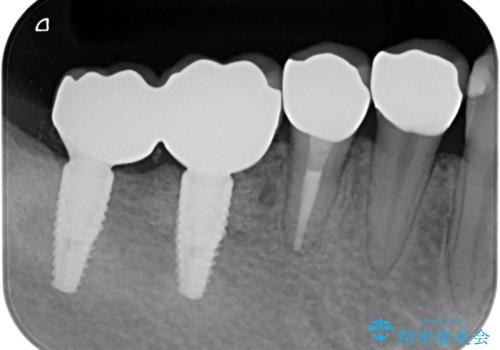

虫歯に伴い歯槽骨の吸収も見られたので造骨後、インプラントを用いて咬合機能を回復します。

- 110万円(インプラント×2・チタンカスタムアバットメント×2・ジルコニアクラウン×2・仮歯×2・遊離歯肉移植術)費用は治療当時の料金となります